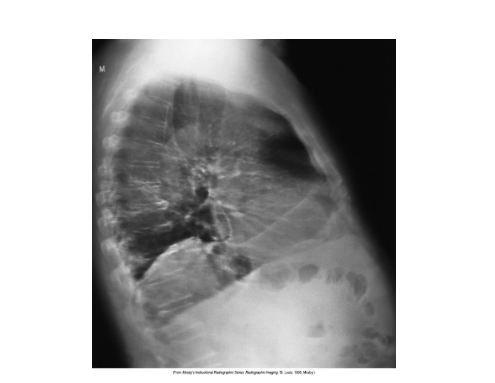

Lateral chest xray is the image

What does the left image and right image show

Voluntary and involuntary motion